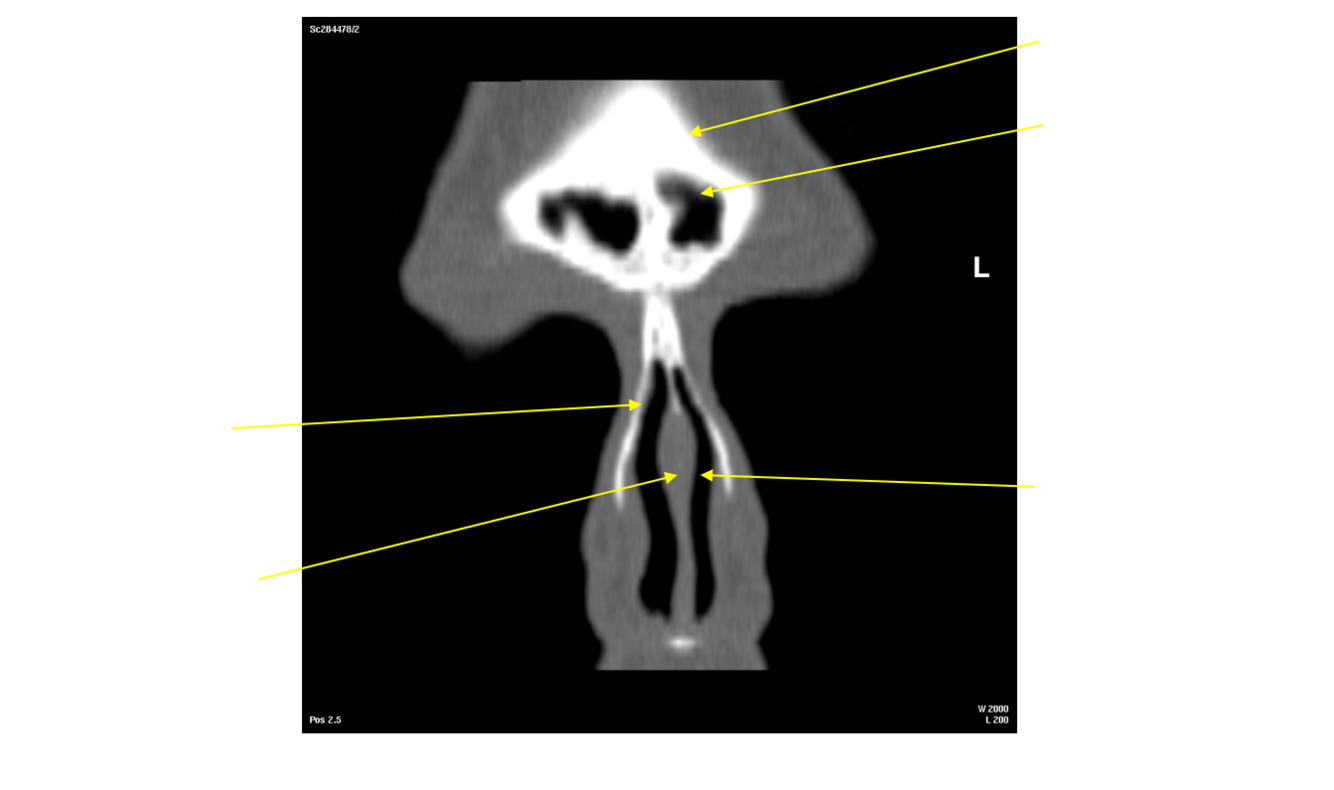

Label the nasal septum

Label this image